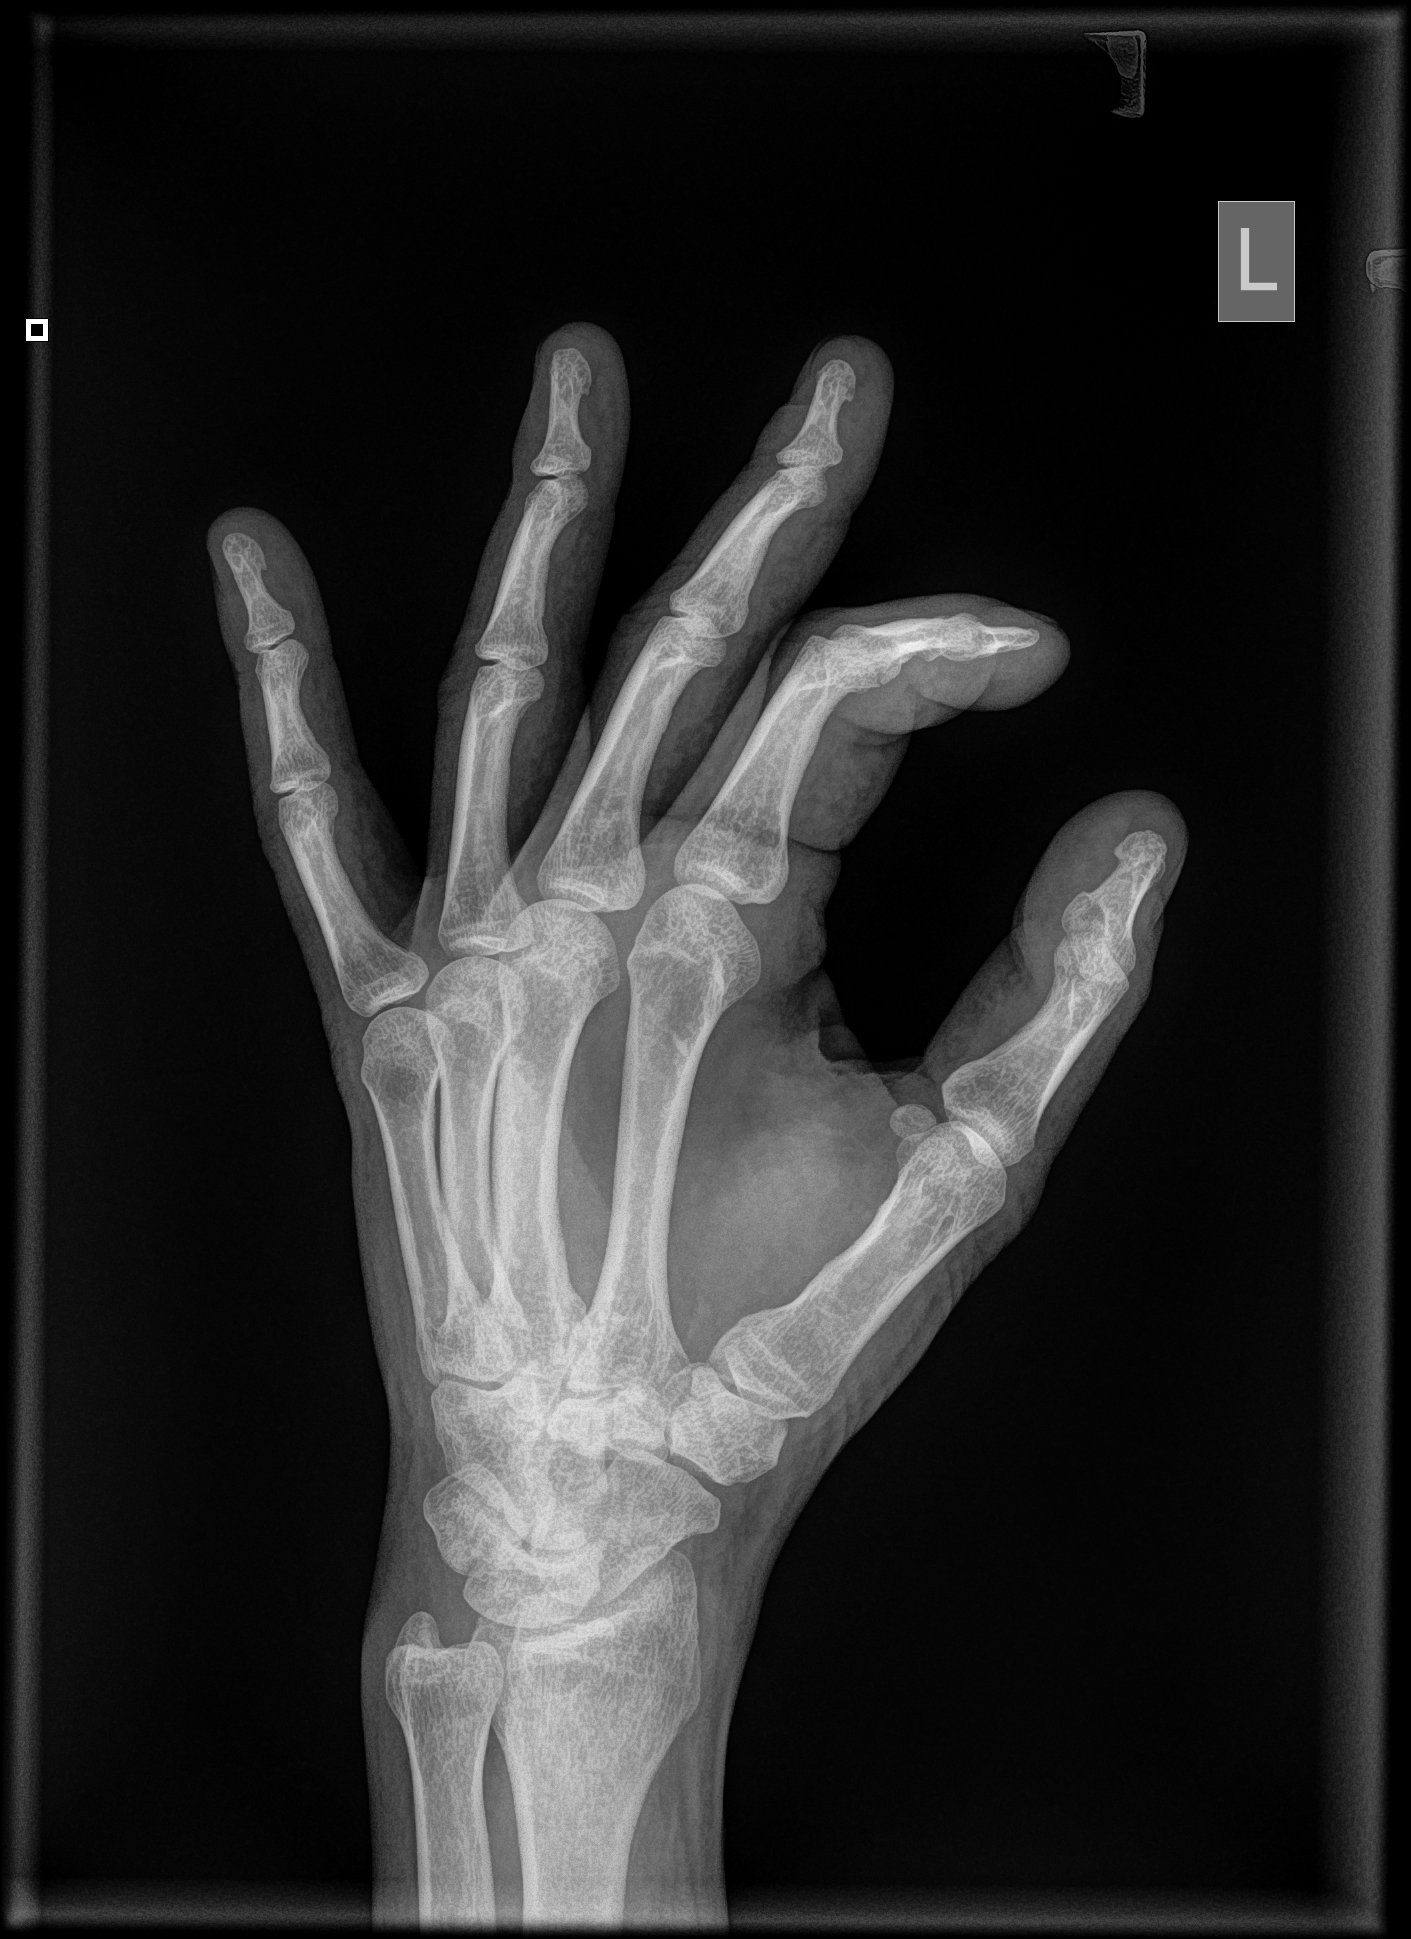

Uszkodziłem sobie palca wskazującego i jest nieco opuchnięty. Bardzo mocno wygiął mi się w górę, aż chrupnęło. Trochę boli mnie na wszystkich zgięciach. Wizytę u ortopedy mam za parę dni, a chciałbym się dowiedzieć, czy mam się czego obawiać. Załączam zdjęcia rtg wykonane dzisiaj.